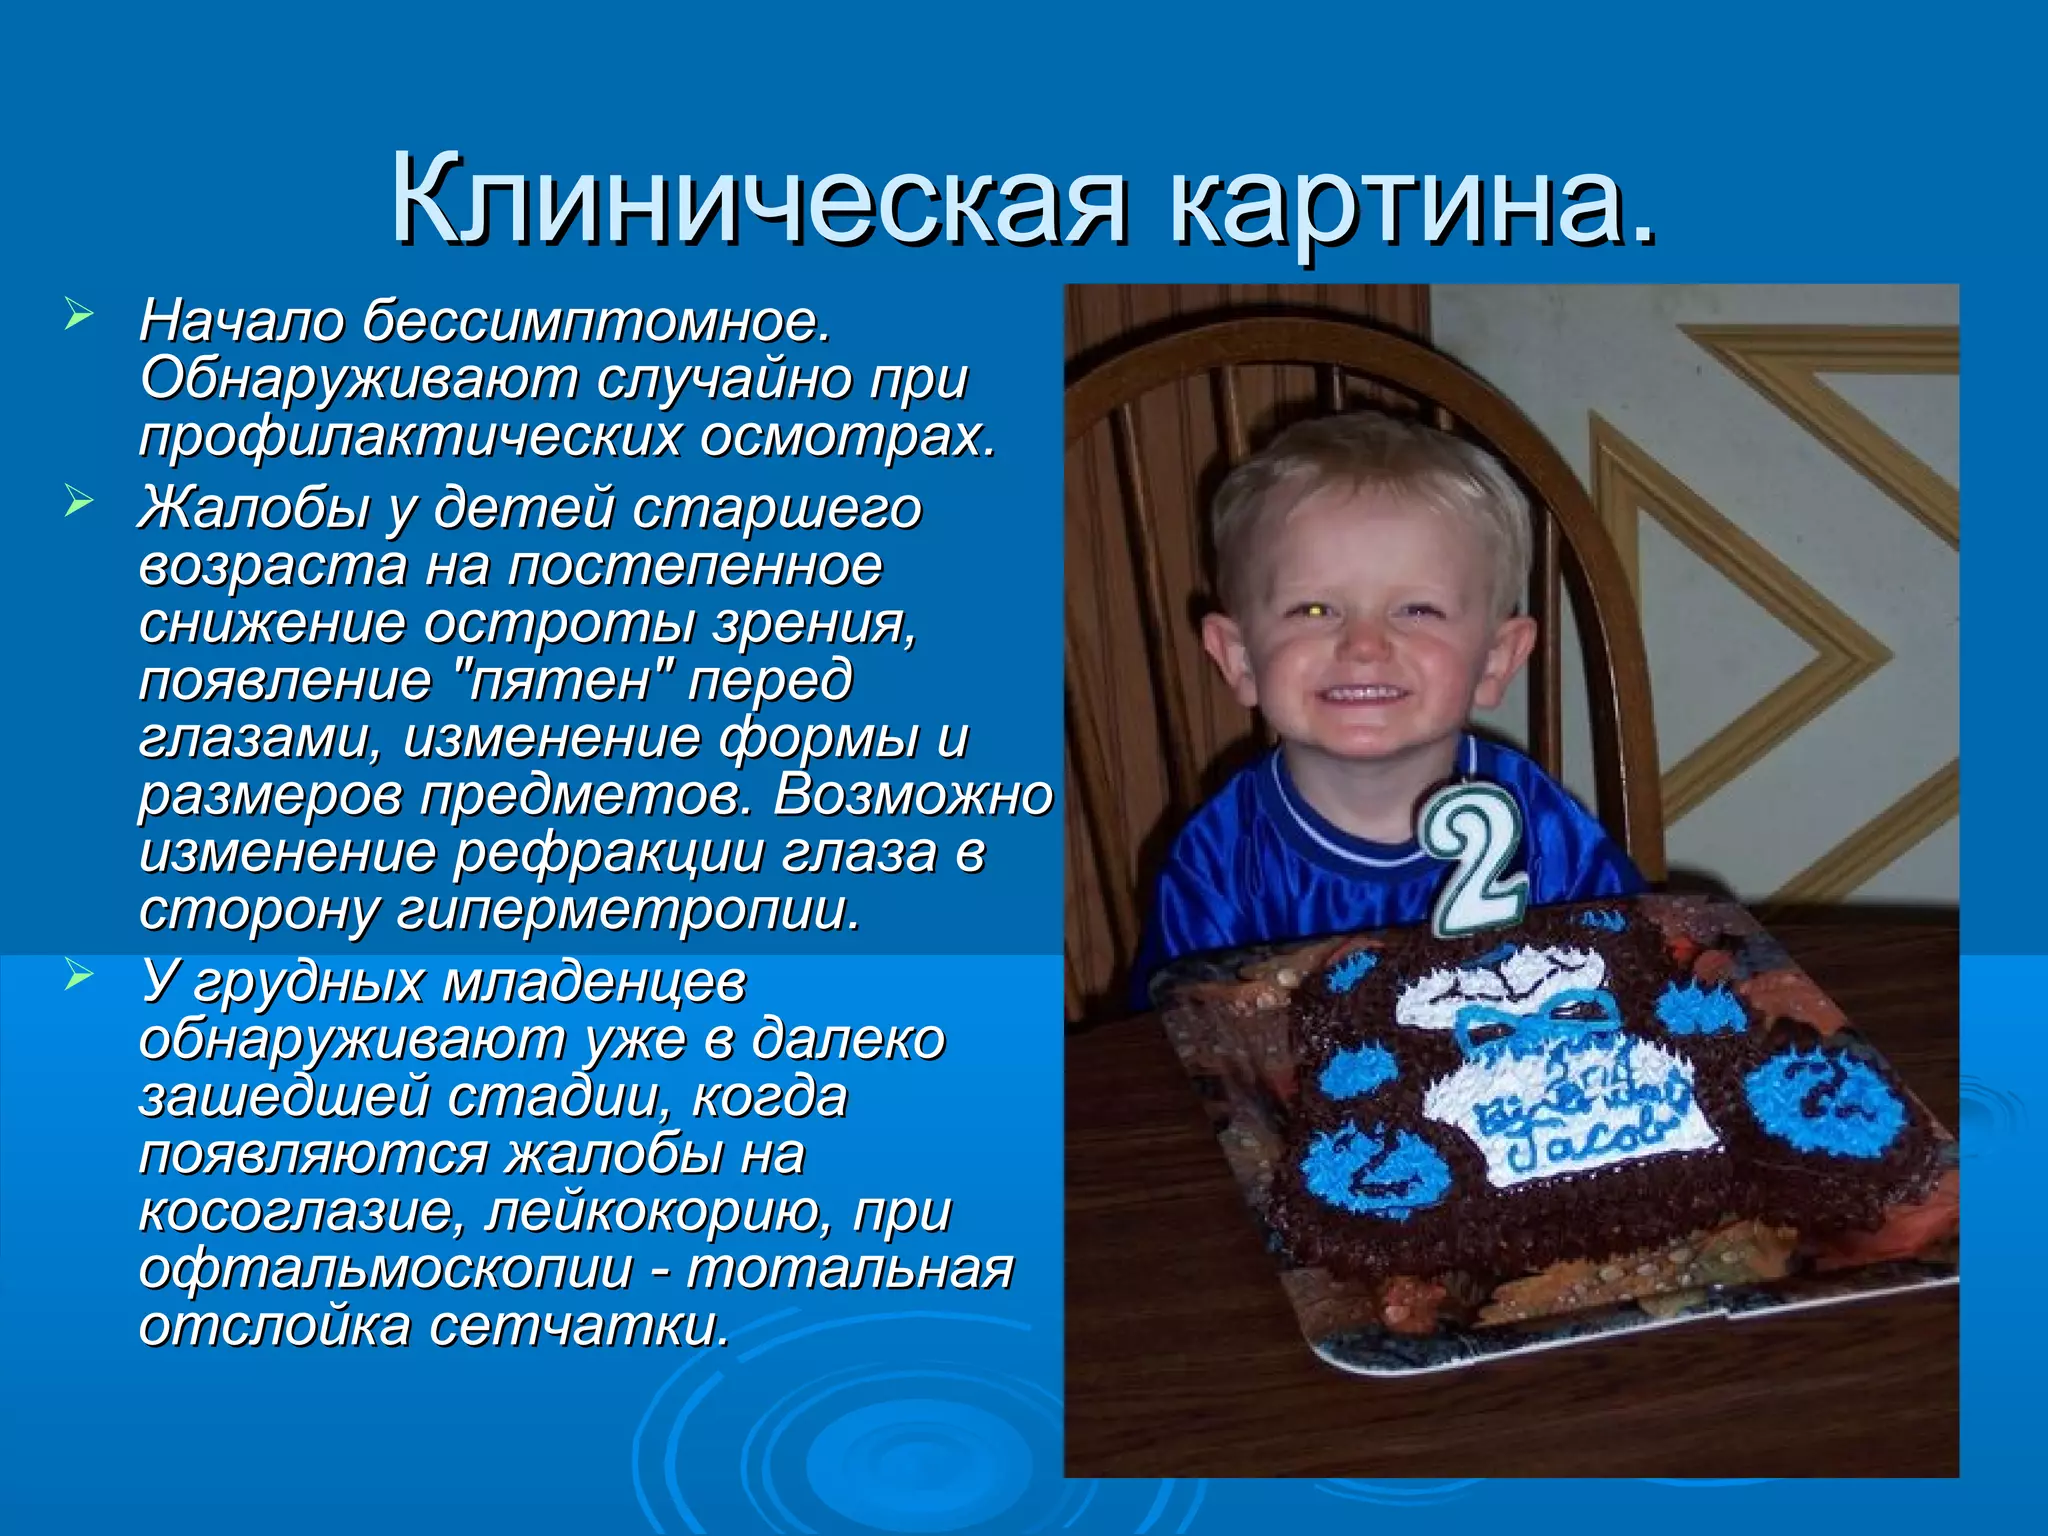

Болезнь Коатса - это идеопатическое заболевание, характеризующееся полиморфными изменениями сосудов сетчатки с массивной экссудацией, чаще всего у детей и подростков, с преобладанием среди мальчиков. Эпидемиология показывает, что заболевание проявляется, как правило, в возрасте 8-16 лет, но возможно его обнаружение и у взрослых. Основные проявления включают ретинальные аномалии, субретинальную экссудацию и постепенно прогрессирующую потерю зрения.